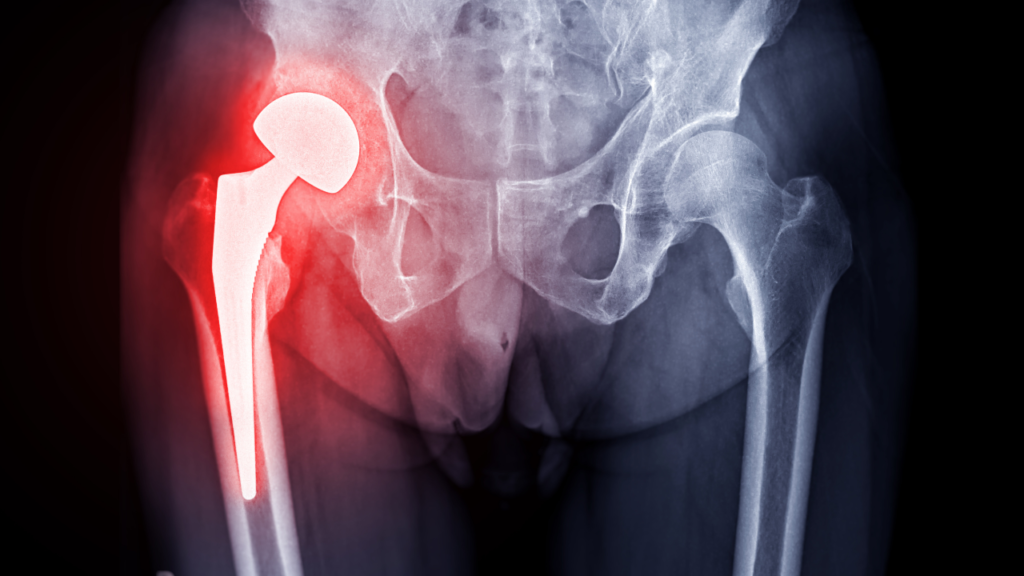

変形性股関節症は、関節軟骨の減少や骨の変形によって引き起こされる疾患で、日本では約100万人の方がこの病気に悩まされています。特に女性に多く見られ、その背景には「臼蓋形成不全症」や「肥満」「加齢」などの要因が関係しています。

臼蓋形成不全症とは、股関節の受け皿である「臼蓋(きゅうがい)」が正常よりも小さい状態を指します。臼蓋が小さいことで股関節にかかる負荷が大きくなり、関節軟骨がすり減りやすくなったり、骨が変形したりするリスクが高まります。